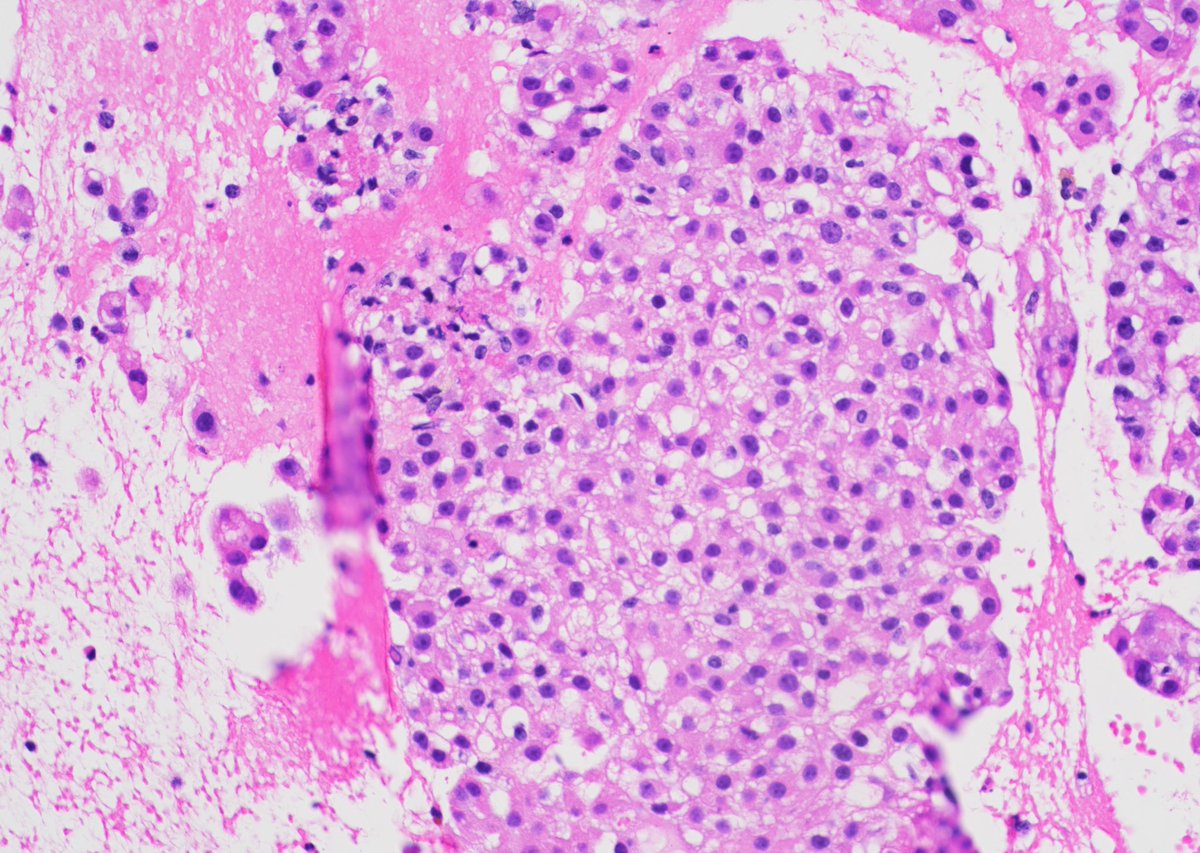

Metastatic GIST to an abdominal lymph node- With both epithelioid and spindle cell features. Positive for DOG1, CD34 and CD117(shown here). #pathtwitter #cytology #surgpath #path Kevin Kuan